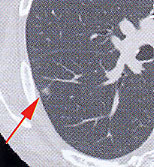

【画面左】

症例1.胸部X線写真では指摘困難だが、CTで淡い濃度の陰影として検出された肺がん。